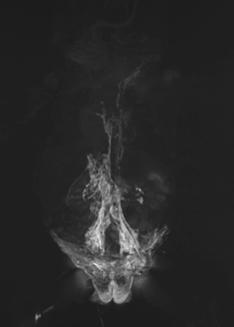

Maximum intensity projection (MIPs) images from DOTATATE PET/CTs before and after treatment with peptide receptor radionuclide therapy (PRRT). Baseline DOTATATE PET demonstrates numerous sites of markedly avid positive disease indicating the patient is a candidate for PRRT.  Post-treatment imaging demonstrates improvement in the extent of disease, although extensive residual disease.

Pascual's care team included medical oncologist Claire Mulvey, MD, and radiologist Thomas Hope, MD, who worked closely together throughout the course of his treatment, which included Peptide Receptor Radionuclide Therapy (PRRT). PRRT is a molecular therapy often used to treat neuroendocrine tumors (NETs) using a radioactive substance that is attached to a peptide designed to bind to receptors on the surface of tumor cells.

“For Jonathan, although PRRT has not removed the majority of his tumors, stabilizing his disease has allowed him to do the things that he enjoys,” said Hope.

“I am amazed by the joy that Jonathan brings to life. He does not let his cancer define the road he will travel,” Hope added. “We often see our patients through the images we take, but there is no relationship between Jonathan’s smile and what one can only call extensive metastases on his imaging.”

Peptide Receptor Radionuclide Therapy

Peptide Receptor Radionuclide Therapy (PRRT) is a targeted cancer treatment that uses a radioactive substance (radionuclide), attached to a peptide (DOTATATE), to deliver radiation directly to neuroendocrine tumors (NETs).

How PRRT works:

The peptide is designed to bind to somatostatin receptors found on the surface of certain cancer cells. The radionuclide, Lutetium-177, a radioactive isotope that emits radiation, when attached to the peptide, delivers radiation directly to a patient’s tumor cells to treat the tumor.

PRRT is commonly used to treat patients with advanced or metastatic neuroendocrine tumors to control tumor growth, reduce symptoms, and may improve quality of life for patients. There are no available FDA approved therapies to treat paraganglioma, but PRRT can be an effective therapy in a subset of these patients.